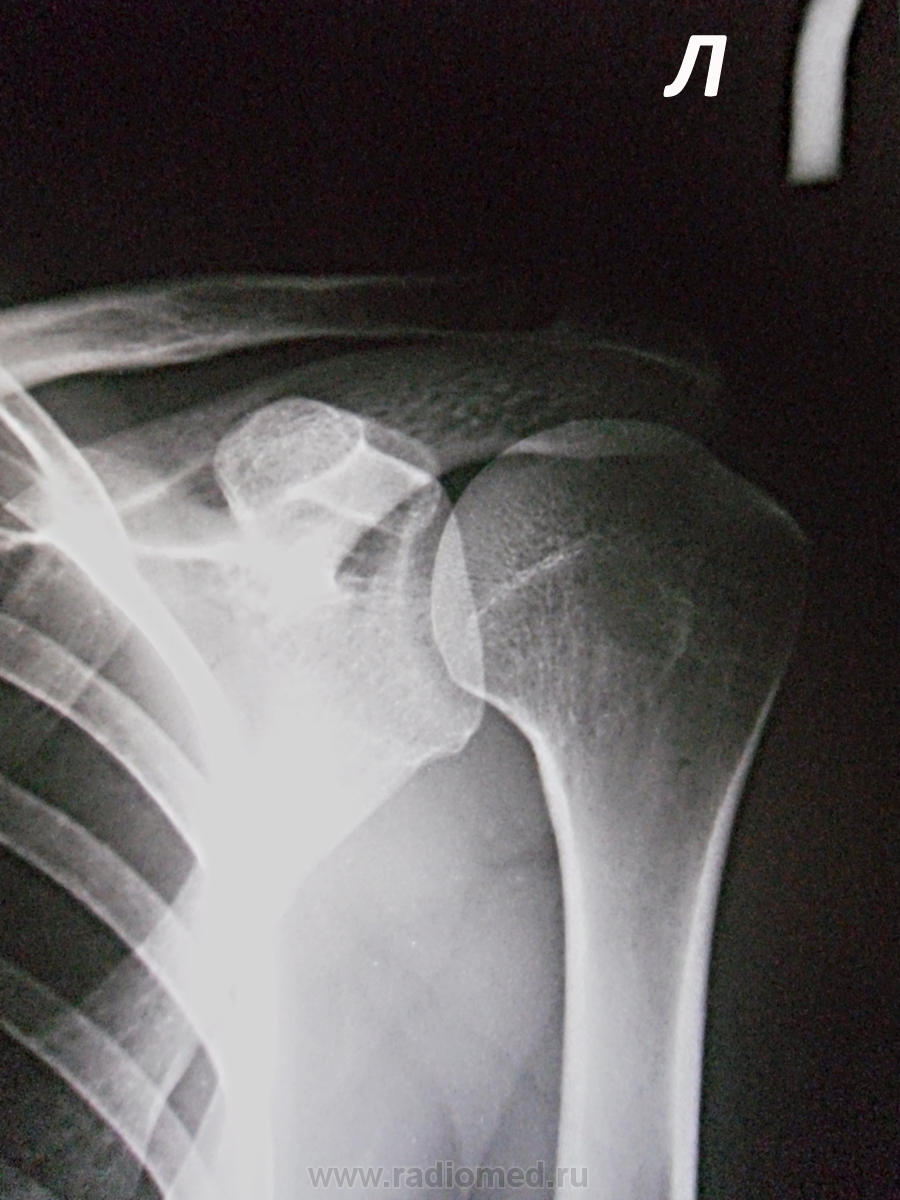

Оцените суставы. Женщина, 31 год. Снимки для МСЭ. Жалобы на боль в правом надплечье и руке, онемение и мышечную слабость руки. Выше мнение?

справа - объем плечевой головки уменьшен, форма ее несколько уплощена, контуры ровные и четкие, проксимальный диафиз уменьшен в диаметре. Суставная впадина полнистая, "скрученная", усиленно склерозированная. Суставная шель расширена до 6 мм, неровномерная. Положителен вакуум-симптом. Умеренно выражен регионарный петлистый остеопороз шейки лопатки, прозрачность проксимального конца плечевой кости повышена. Клювовидный отросток лопатки удлинен...

Отчего же "навязчиво". Да, укладки с разницей в повороте на 15, однако режим РГ и ф.р. одинковы. Да и потом, каждый из нас знает, что оригинал пленки - это не цифровая джипежка, -  уж остеопороз, поверьте, отличить от нормы могу. Тем более, что он там ЕСТЬ. При заключении остеопороз, как и положено, полагаюсь не на прозрачность (черное/белое может широко варьировать), а на структуру, в которой "количество костных балок на единицу площади уменьшено". А в заключении написал: атрофия правого плечевого сустава, вероятно, нейротрофического генеза, слева - артроз 1 стадии. Затем затребовал карточку и обнаружил: инвалид детства 3 группы, родовое повреждение плечевого сплетения справа Дюшена - Эрба. Так что коллега helenmar на высоте.